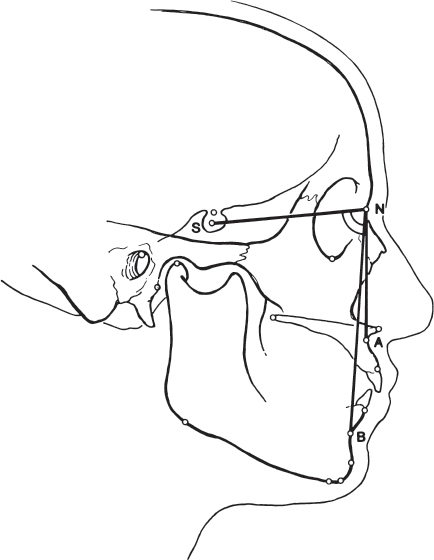

The assessment of craniofacial dimensions is important in diagnosing structural facial dysharmony. Attempts have been made for years by artists, surgeons, and orthodontists to analyze and quantify the proportions of the face. Cephalometry, the scientific measurement of the dimensions of the head, was first used in orthodontics to assess craniofacial growth. Another method for craniofacial analysis based on cephalometry is cephalometric radiography. Although cephalometric radiography was originally introduced into orthodontics during the 1930s, widespread acceptance of the method has only occurred during the past 20 years. 3 In 1931, Hofrath and Broadbent simultaneously and independently developed methods for the production of standardized cephalometric radiographs. 4 This standardization is achieved using a specialized device, known as a cephalostat, which holds the head in a fixed and reproducible position ( Fig. 70.7 ). 5 The cephalostat stabilizes the head with three rods. One rod fits in each external auditory meatus, and a third rod rests passively on the inferior orbital rim or the nasofrontal suture. The radiograph taken is a true lateral view, with no head rotation in the sagittal plane. The cephalometric film should be taken with soft tissue technique to most clearly demonstrate the relationship between the soft tissues and the facial skeleton. 6 To further standardize the radiograph and to minimize distortion, a consistent subject-to-film distance and X-ray target-to-subject distance must be used.

The cephalometric radiograph obtained provides a twodimensional outline of the lateral aspect of the craniofacial skeleton ( Fig. 70.8 ). It can be traced onto a matte acetate sheet to provide a model on which various analyses may be performed. However, this radiograph is subject to image distortion. The acetate model is also subject to tracing error. The purpose of the cephalometric tracing is to provide objective data that assist in the diagnosis and treatment of facial skeletal deformities.